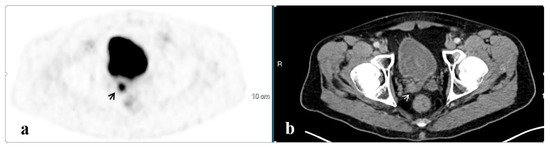

3.4. Salvage Radiation Therapy

3.4.2. The Site of Salvage Radiotherapy

| Pelvic bones | 16 | 14.2 ± 18.2 | 2.0 ± 1.0 | 2 |

| PF | 7 | 5.8 ± 5.6 | 1.4 ± 0.4 | 2 |